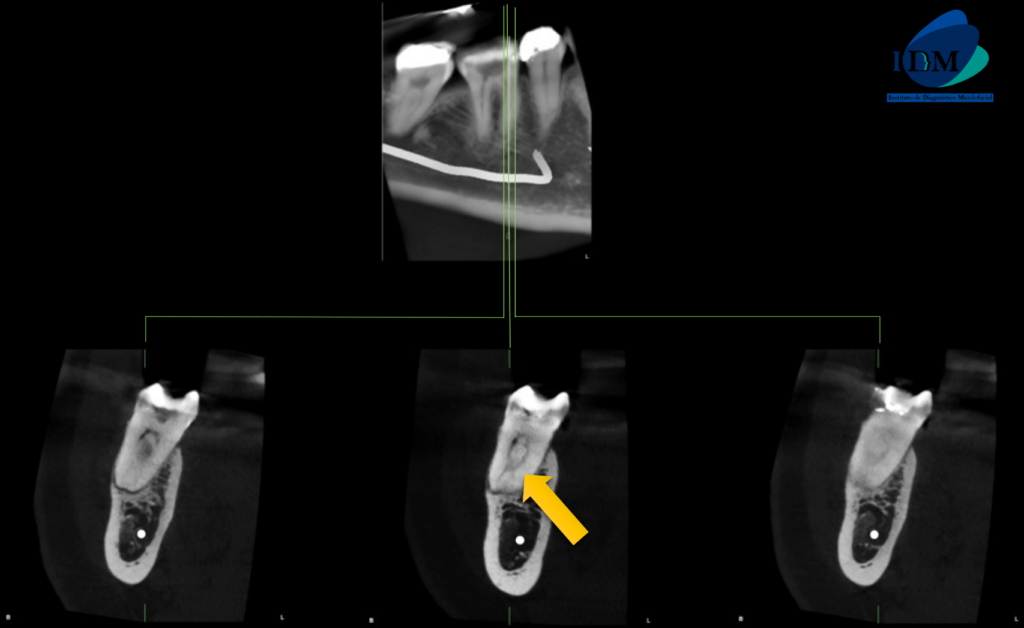

A La evaluación de la tomografía computarizada de campo reducido de la pieza 46 se observa material restaurador coronario amplio, una cavidad cameral amplia y ensanchamiento del espacio para el ligamento periodontal periapical en ambas raíces con el aumento de la densidad ósea compatible con osteítis circundante.

Sin embargo respecto a la conformación de los conductos pulpares podemos observar que la raíz mesial presenta un conducto colateral hacia palatino que a su vez confluye con el conducto pulpar principal para nuevamente separarse, todo esto a nivel del tercio apical.